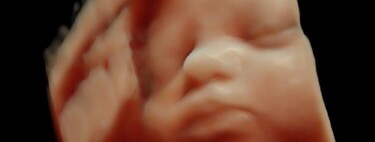

Una embarazada compartió una imagen de la ecografía de su bebé y se dio cuenta que era igual a la de otras mujeres que habían ido a la misma clínica privada. "¡Tengo la misma foto!", denunciaron en redes sociales.

Son madres que viven en la provincia de Formosa, Argentina, y denuncian que han jugado con sus ilusiones al entregarles una prueba falsa de su embarazo, ya que el bebé que aparece en la ecografía 5D se repite en varias de ellas.

Una de ellas lo compartió en Twitter, enseñando al menos tres ejemplos de ecografías idénticas: “Por ahora somos tres mamás a las que una clínica ESTAFÓ con una foto de un bebé que no es el nuestro”.

Por ahora somos 3 mamás a las que una Clinica ESTAFÓ con una foto de un bebé que no es el nuestro, está de más decir que encima que cobran carísimo uno se va ilusionado por ver a su bebé y tener un lindo recuerdo. Estamos en busca de más mamás con el mismo bebé🥺 pic.twitter.com/yKFq2neE0A

La denuncia se hizo viral tanto en Twitter como en Tik Tok, y aparecieron al menos una decena de familias que se sumaron a la denuncia al darse cuenta que tenían las mismas imágenes con los distintos nombres de sus bebés, tanto de niños como de niñas.

Según contaron las supuestas estafadas, se les tomaban los datos al llegar, ingresaban a una sala donde se les realizaba la ecografía y unos minutos después se les entregaba un informe impreso con la captura de la carita de su supuesto bebé. Todo parecía normal hasta que se dieron cuenta de la estafa gracias a otras madres.

Las ecografías 5D son imágenes tridimensionales de alta resolución hiperrealistas obtenidas a través de ultrasonidos. Además de su valor diagnóstico para detectar cualquier detalle sobre la evolución del feto, tiene un alto componente emocional, ya que permite observar al bebé en movimiento dentro del útero en tiempo real, haciendo gestos, sacando la lengua, bostezando . Son las primeras imágenes que tienen los padres de su bebé antes de poder tenerlo en brazos.